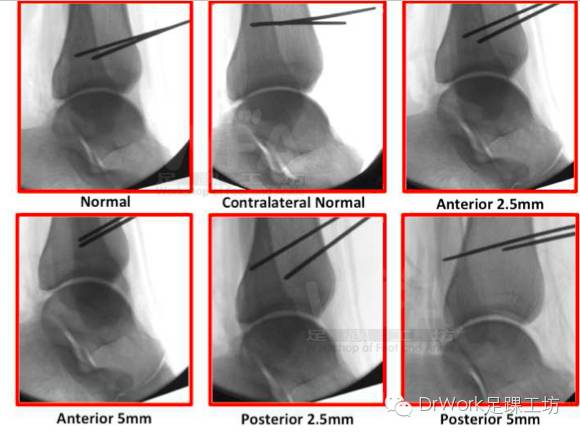

复位后与健侧对比可显著提高复位准确率

• 健侧

• 患侧

• 术中复位后正位片、侧位片与健侧对比